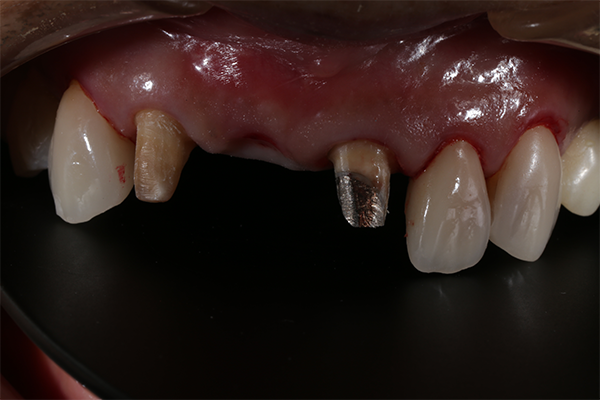

前歯部をオールセラミックによる審美的、機能的な回復をはかったケースです。

前歯ということで歯ぐきのラインにも気をつけより自然な仕上がりにしました。